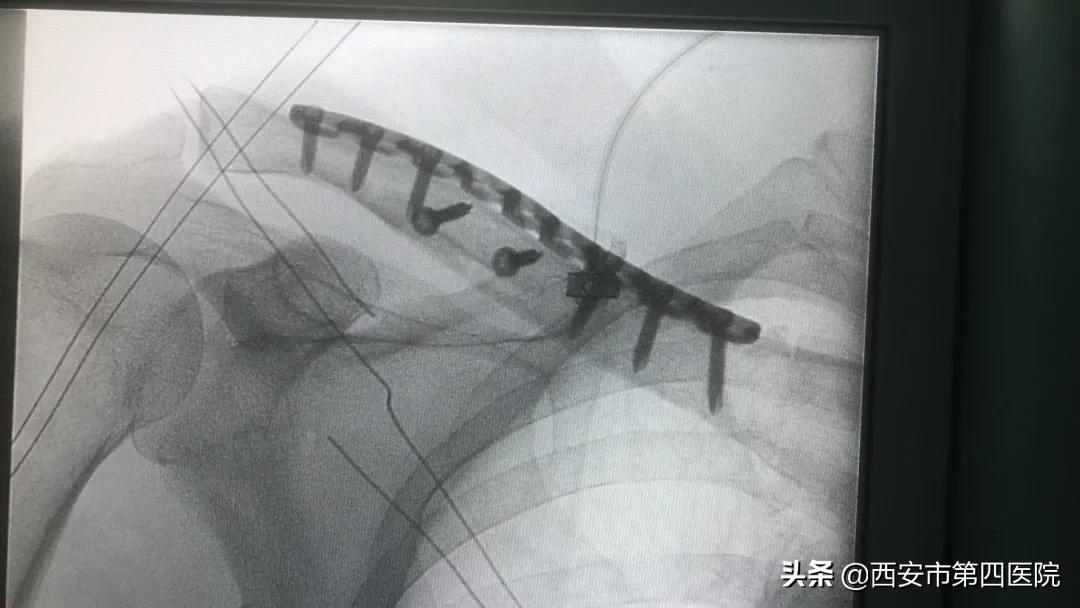

术中X线片

该患者入院后,骨科病院迅速完善术前相关检查。2月25日,在经验丰富、显微外科技术尤为突出的祝勇刚教授指导下,在航天城院区手术室护理团队、麻醉与围术期医学中心团队的全力配合下,顺利完成此例保留锁骨上皮神经锁骨骨折切开复位内固定术。目前患者情况平稳,恢复状况良好。